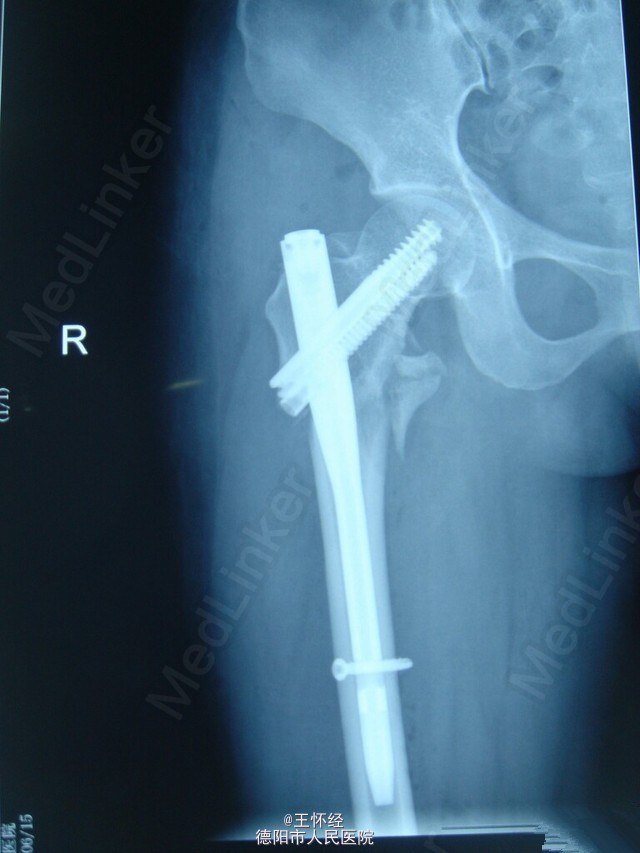

右侧股骨转子间骨折

患者女性,28岁,车祸伤急诊入院,右腿疼痛不能活动,x线检查发现转子间骨折。

右股骨转子间骨折

右侧转子间骨折